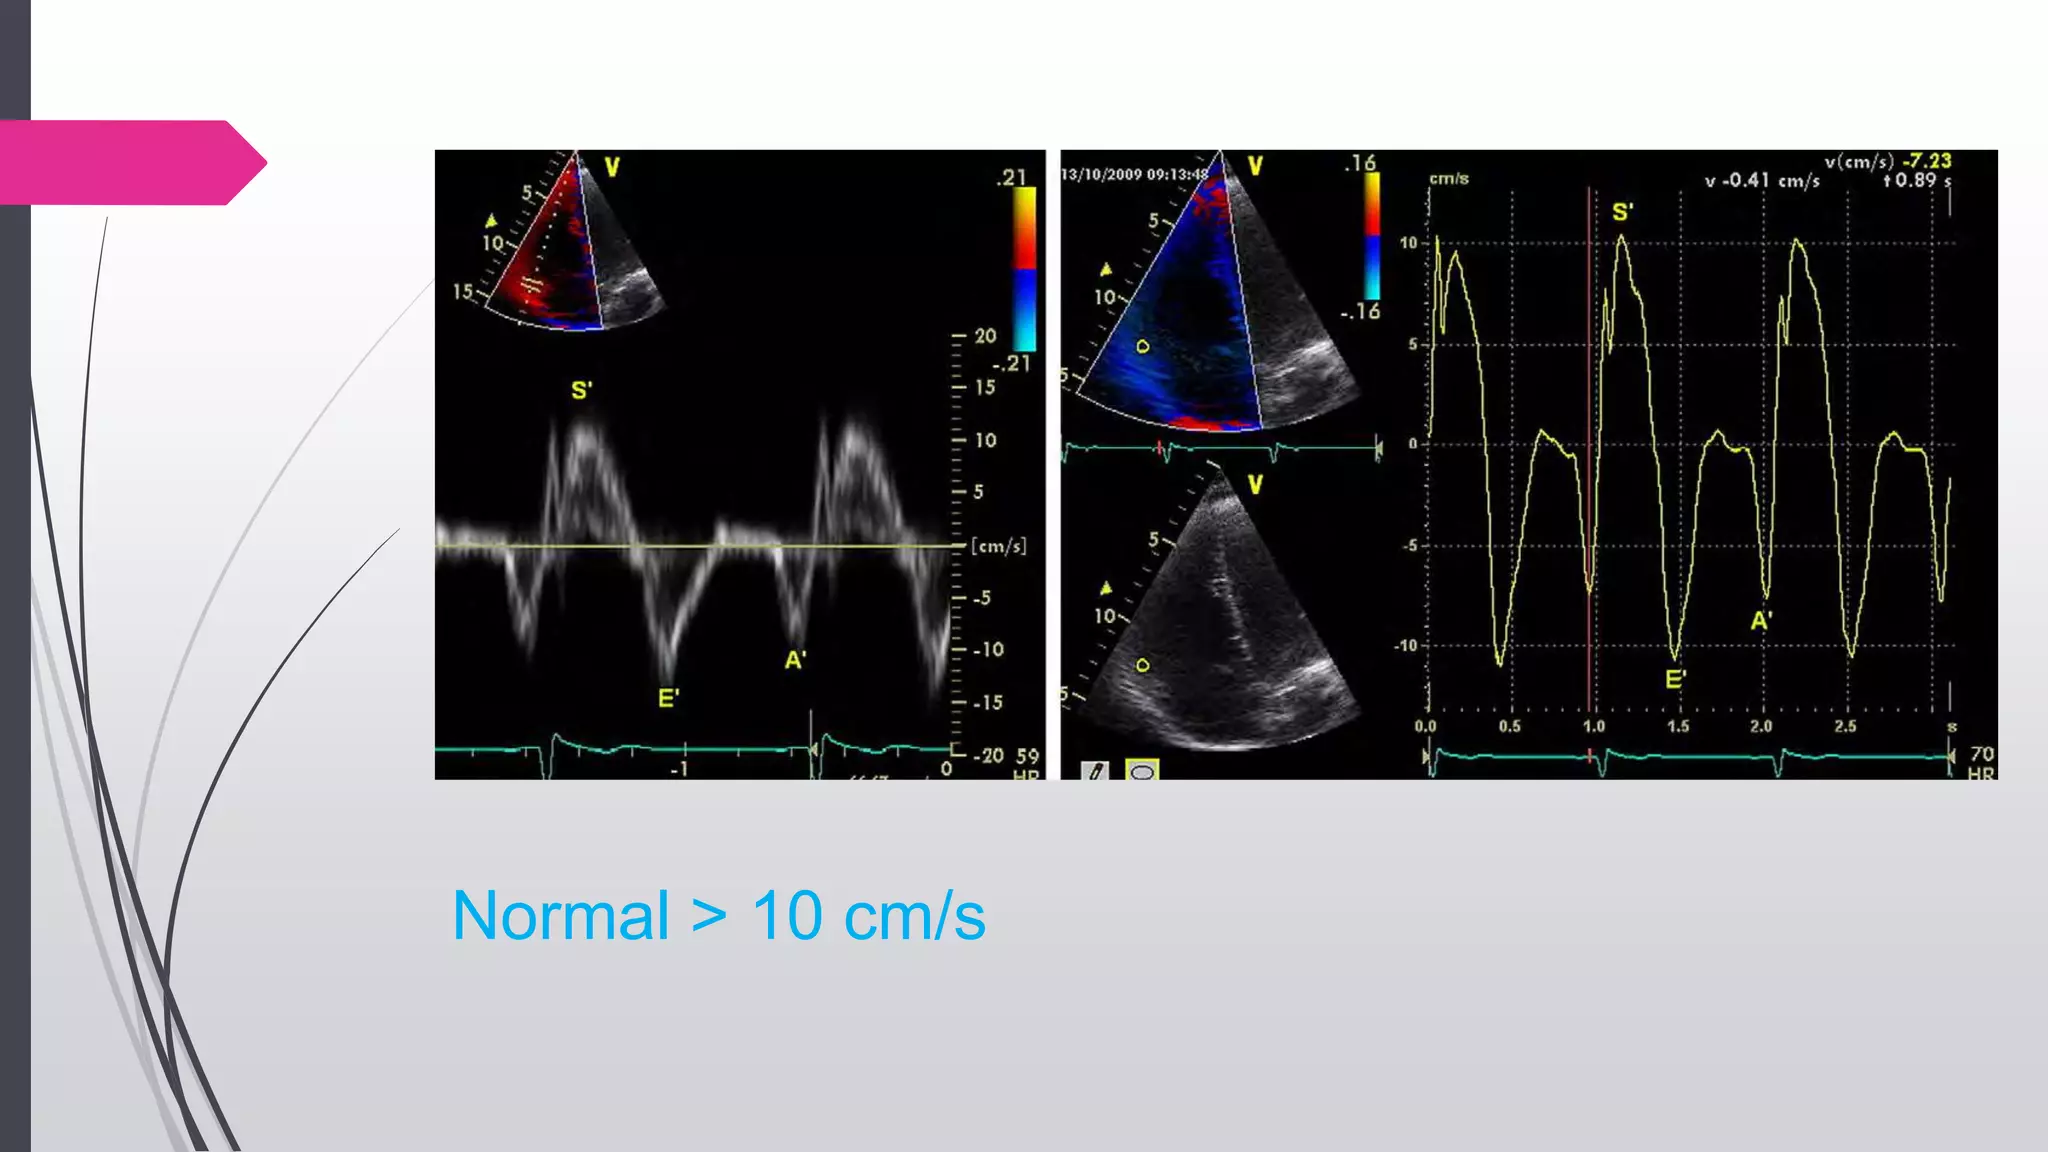

TISSUE DOPPLER IMAGING

 An apical four chamber view is used

 The pulsed Doppler sample volume is placed in either the tricuspid

annulus or the middle of the basal segment of the RV free wall

 The S´velocity is read as the highest systolic velocity without over-

gaining the Doppler envelope

Normal > 10 cm/s

Advantages

 A simple, reproducible technique

with good discriminatory ability to

detect normal versus abnormal RV

function

 Pulsed Doppler is available on all

modern systems

 Maybe obtained and analyzed off-

line

Disadvantages

 Less reproducible for non basal

segments

 Is angle dependent

 Limited normative data in all ranges'

and in both sexes

 It assumes that the function of a

single segment represents the

function of the entire right ventricle